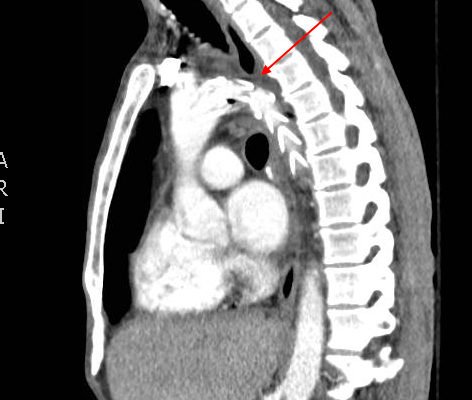

Traumatic Aortic Injury

DOI: https://doi.org/10.21980/J85P4JThe initial chest x-ray showed an abnormal superior mediastinal contour (blue line), suggestive of a possible aortic injury. The CT angiogram showed extensive circumferential irregularity and outpouching of the distal aortic arch (red arrows) compatible with aortic transection. In addition, there was a circumferential intramural hematoma, which extended through the descending aorta to the proximal infrarenal abdominal aorta (green arrow). There was also an extensive surrounding mediastinal hematoma extending around the descending aorta and supraaortic branches (purple arrows).